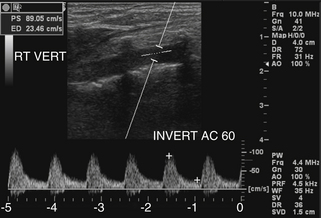

Существует ряд других гемодинамических состояний, которые могут привести к аномально сильному или сильно ускоренному кровотоку в позвоночных артериях. Самый распространенный из них был упомянут ранее, а именно наличие доминирующей позвоночной артерии, чаще всего встречающейся с левой стороны. Значительное увеличение скорости движения позвоночных артерий также может наблюдаться, когда одна или обе позвоночные артерии являются компенсаторным механизмом окклюзионного заболевания в других частях цереброваскулярной системы ( рис. 11-7 ). Это может быть следствием окклюзии или почти окклюзии внутренней сонной артерии или контрлатеральной позвоночной артерии или может представлять собой компенсаторный поток из подключичной обкрады в контралатеральную позвоночную артерию. В редких случаях в среднем сегменте позвоночной артерии могут обнаруживаться высокоскоростные турбулентные потоки из-за внешней компрессии со стороны костного отдела позвоночника (часто связанной с изменениями положения головы или шеи, часто называемой «синдромом охотника за луком»), сужения просвета позвоночной артерии. вследствие васкулита или атеросклеротического стеноза средней позвоночной артерии. Диссекция позвоночной артерии обычно не связана с повышенной скоростью кровотока при отсутствии значительного сужения истинного или ложного просвета ( рис. 11-8 и 11-9 ).

РИСУНОК 11-9. Цветное и спектральное допплеровское изображение расслоения позвоночной артерии с практически нормальными характеристиками кровотока, отмеченными в истинном просвете. Допплеровский сигнал демонстрирует характеристики низкого сопротивления, а пиковая систолическая скорость (PSV; 39,6 см/сек) находится в пределах нормы.